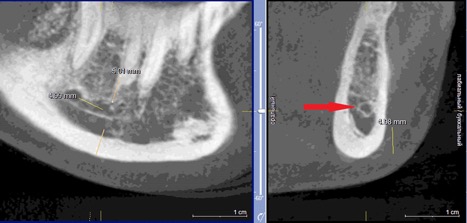

При измерении расстояния от резцовой петли до вестибулярной стенки нижней челюсти и её топографии в области правила «трёх пятёрок», выделено три положения канала, в котором проходит резцовая петля: канал прилежит, т.е. стенка канала образована кортикальной частью (рис 3), касается, т.е. имеет одну общую точку (рис 4) и не имеет общих точек.

Рисунок 4. КЛКТ Сагиттальный и коронарный реформаты переднего отдела нижней челюсти.

Канал соприкасается с кортикальной частью кости (красная стрелка – резцовая петля).